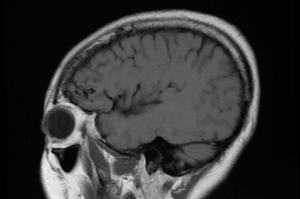

案例(三):血管瘤破裂流血导致肢体无力49岁的女士,接种疫苗后2周感到左腿无力,虽然看了中医和骨科医生,更做了脊柱磁力共振MRI造影, 仍然找不到原因。脑血管外科医生经过临床评估后为她进行了3D三维立体磁力共振脑血管造影,显示其大脑都有先天性动静脉畸形血管瘤并且已经少量出血,瘀血压着她右脑负责控制左腿功能的位置。在3D三维立体电脑导航、运动神经脑皮层反射和连续脑功能监测系统下,神经血管外科医生在显微镜下彻底切除血管瘤和去除瘀血,病人脑部的神经功能得以完好恢复。手术后,病人左腿的力量恢复正常。 | ||

![]() | ||